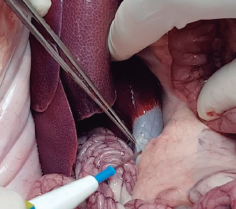

Imágenes y Cirugía

|

María Alfonso García, Alessandro Bianchi, Natalia Pujol Cano, Beatriz Miriam Rodríguez Chikri, Marina Jiménez Segovia, Francesc Xavier González Argente

|

|

|